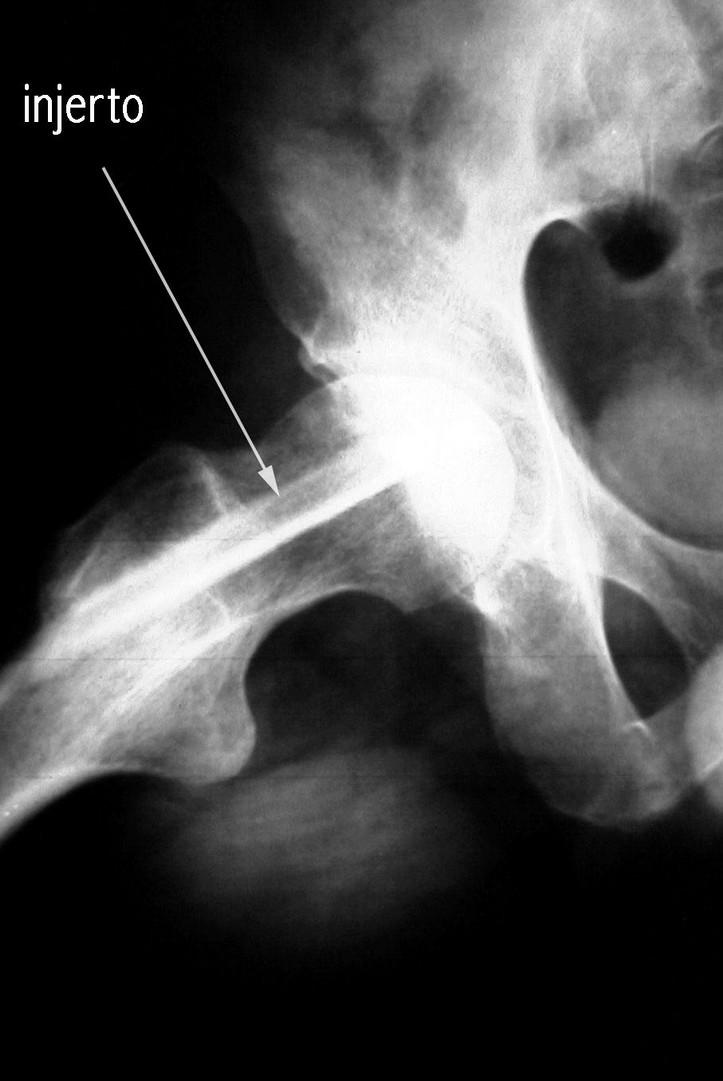

Injerto Óseo No Vascularizado

El defecto de la cabeza femoral puede rellenarse con injerto de hueso antólogo o con diversos sustitutos del injerto óseo.

Injerto de Peroné  descompresión de la cabeza femoral.  resección del hueso necrótico.  sustitución con hueso esponjoso fresco.  soporte del hueso subcondral con un injerto óseo fuerte y viable.  revascularización y osteogénesis de la cabeza femoral

El injerto peroneal con los vasos peroneos se obtiene de la pierna ipsilateral para insertarlo en el cuello y cabeza femoral.

Se obtiene hueso esponjoso del trocánter mayor que se inserta en la cavidad formada tras la extirpación del hueso necrótico. El injerto de peroné se inserta en el túnel y se estabiliza con una aguja de Kirschner de 0.62 mm. La arteria y venas peroneas se anastomosan a las ramas ascendentes de la arteria circunfleja femoral lateral (LFCA) y sus venas satélites.